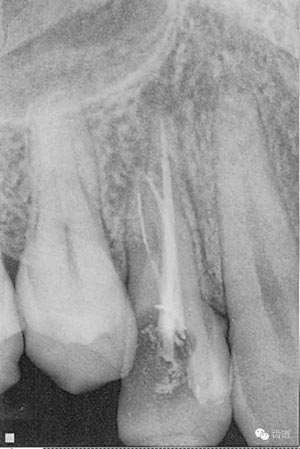

檢查顯示:近頰及腭根充填恰填,遠(yuǎn)頰根管內(nèi)有少許充填物影像。根尖明顯低密度影像。

處理:顯微根管治療。放置橡皮障,去除暫封,顯微鏡下超聲去除頰側(cè)根管上段部分牙本質(zhì),探及遠(yuǎn)中根管口,見(jiàn)有糊劑遮蓋。Path file根管疏通,M Two根管預(yù)備至2506#,配合3%次氯酸鈉和17%EDTA超聲蕩洗,干燥根管,放置氫氧化鈣糊劑,zoe暫封。

處理:放置橡皮障,去除暫封,超聲結(jié)合2%CHX清除遠(yuǎn)頰根管內(nèi)氫氧化鈣糊劑,主牙膠試合后95%酒精沖洗干燥根管,結(jié)合AH Plus糊劑連續(xù)波熱牙膠垂直加壓充填根管,樹(shù)脂分層粘接修復(fù)牙體。建議定時(shí)復(fù)診進(jìn)行嵌體修復(fù),患者未執(zhí)行。